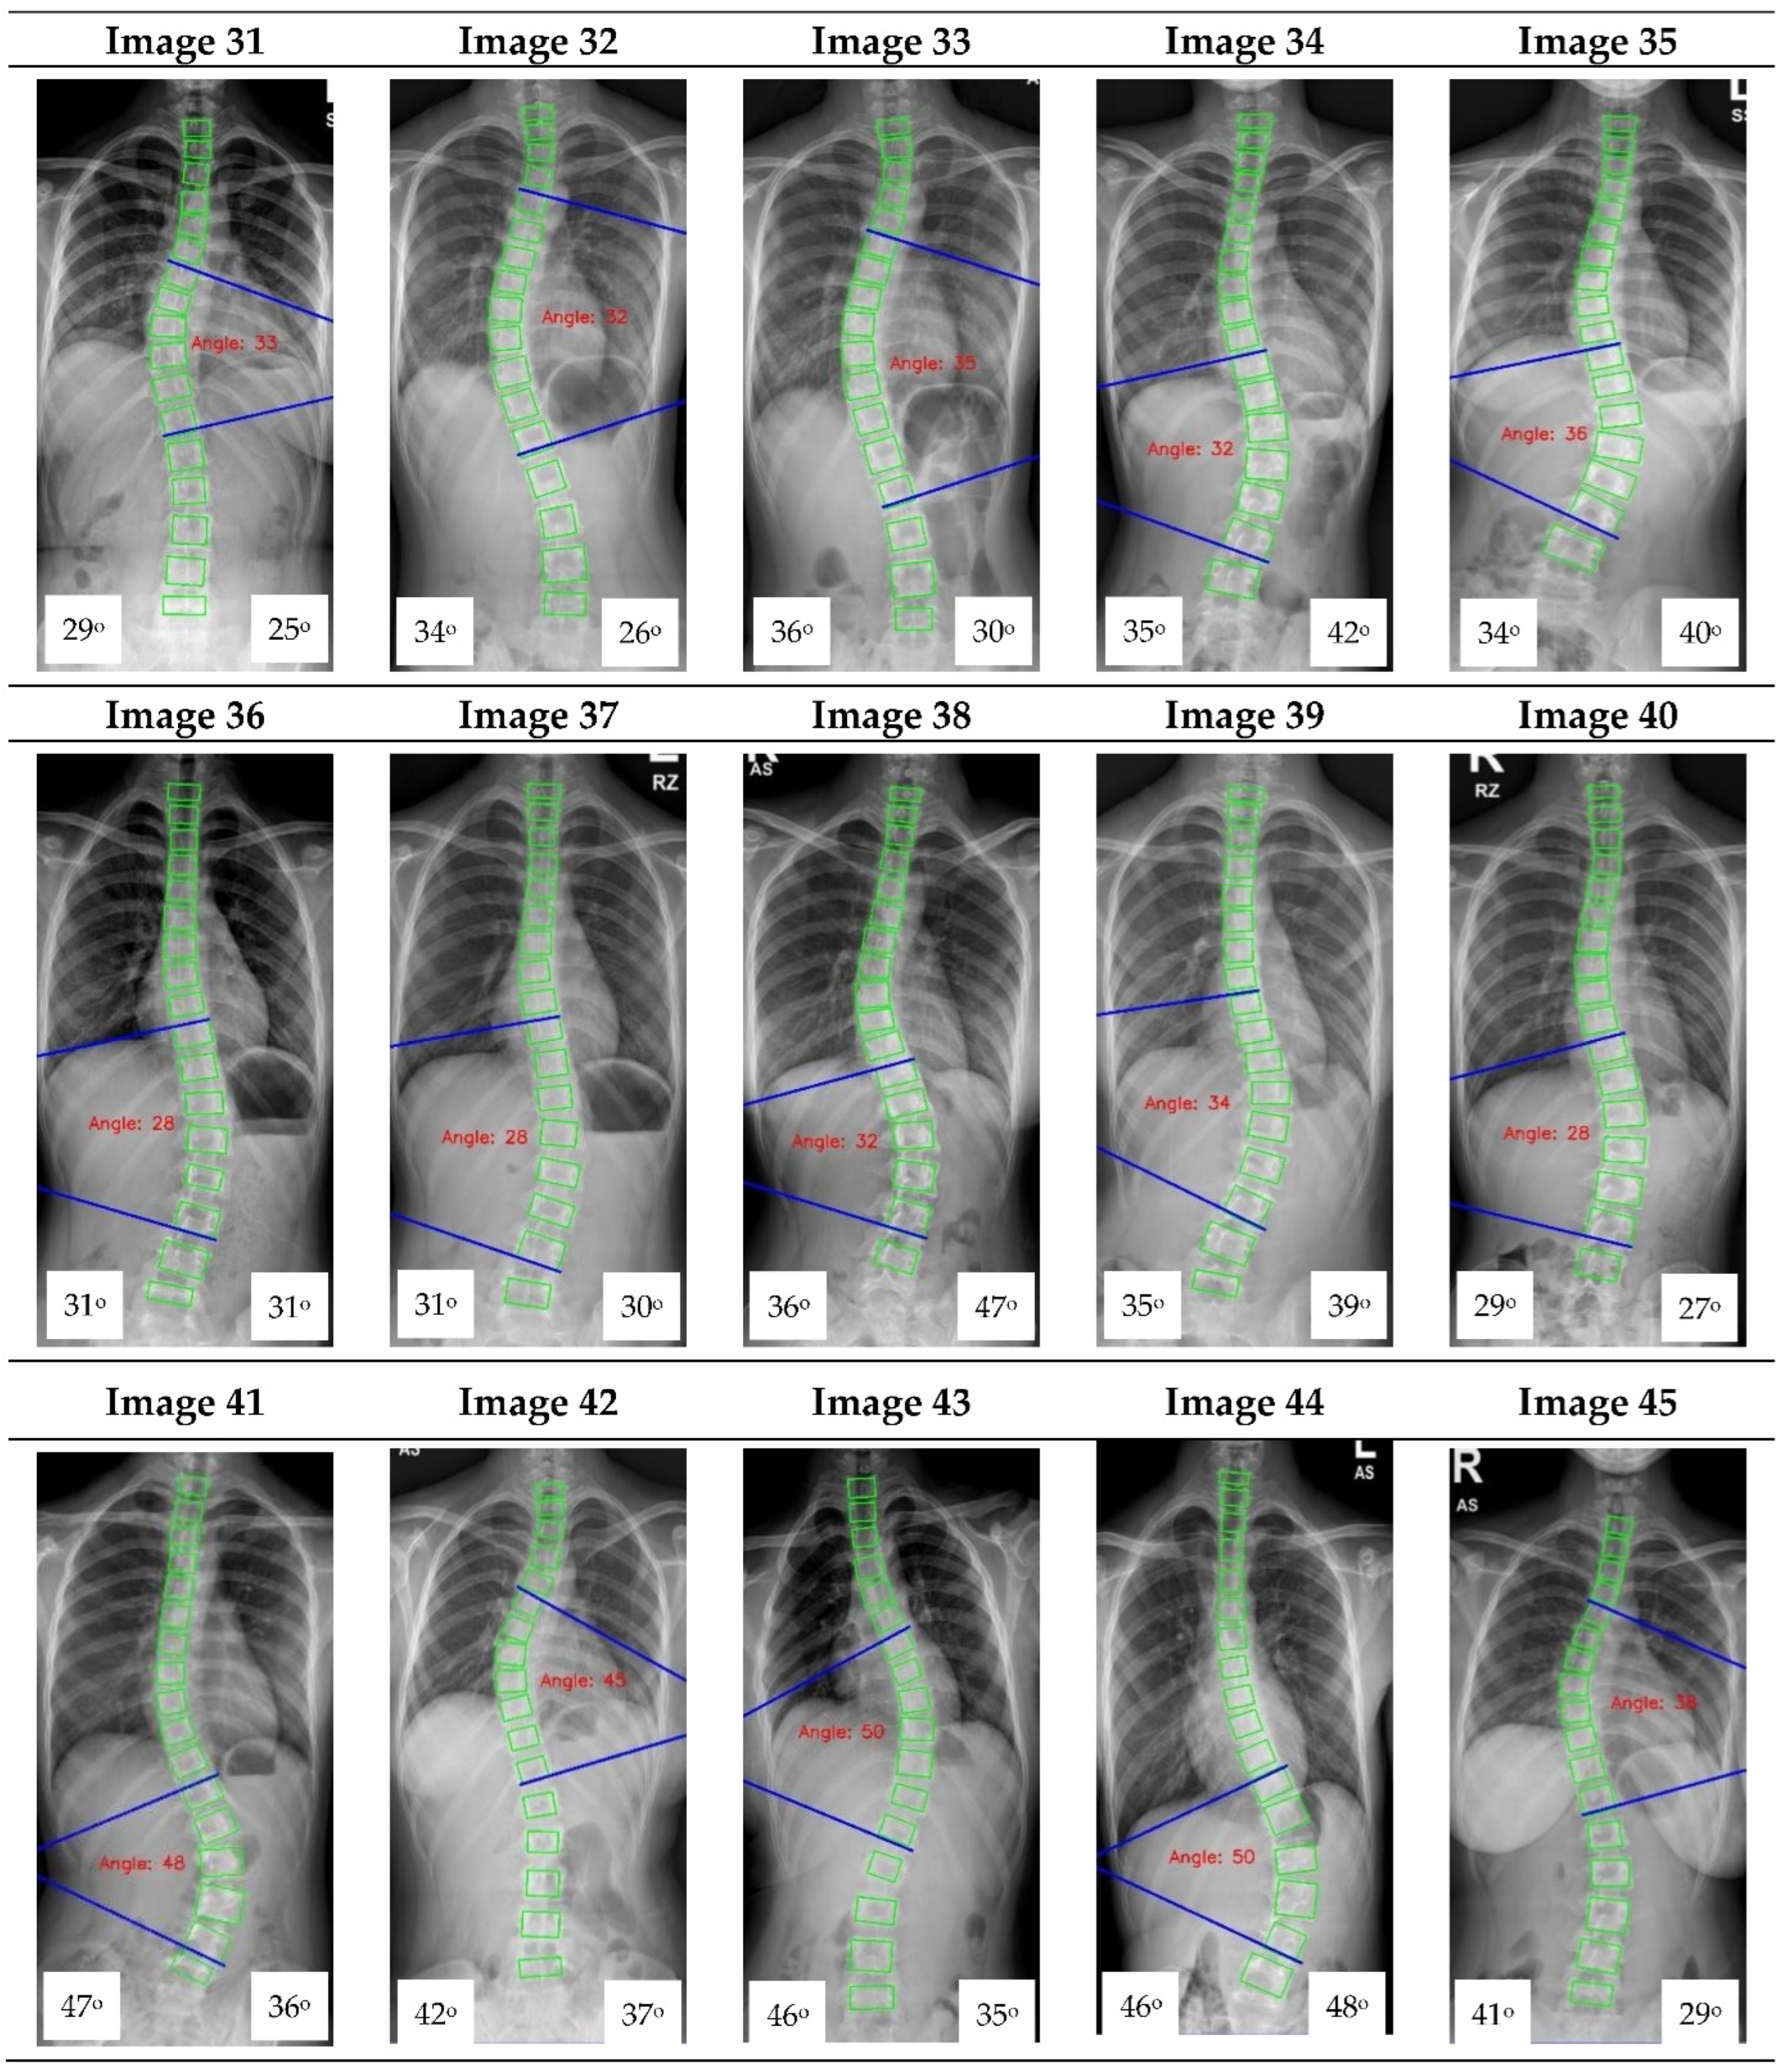

Figure A1.

The red font inside the X-ray image is a CNN CA measurement. Observer 1 and 2 evaluation is presented on the bottom left and right, respectively.